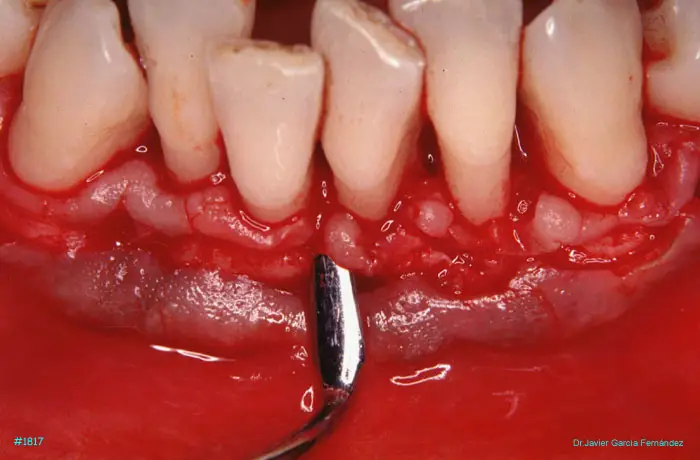

Atlas of Surgical Techniques in Periodontics. CASOS CLINICOS.

Atlas de Técnicas Quirúrgicas en Periodoncia

image 84